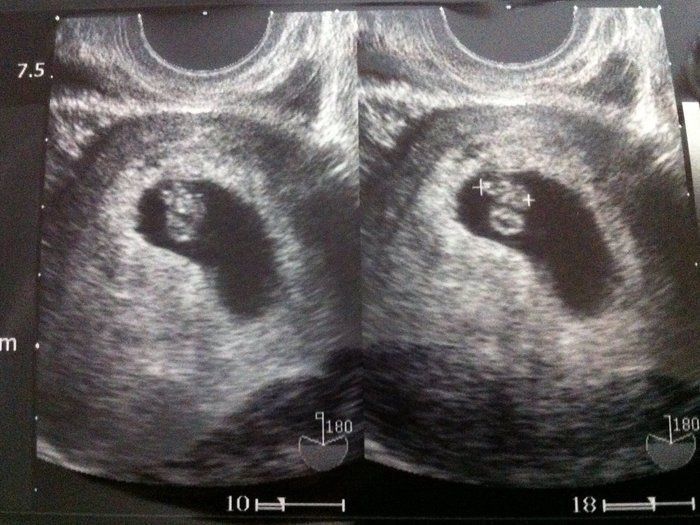

Tomomiさんの妊娠6週目のエコー写真 4日で3.9mmも成長!!

心拍確認から数日後、腰痛と少量の出血が起こり、急遽クリニックへ。「お願い…なんとかしがみついていてね…」と、祈る気持ちで診察を受けましたが、ベビちゃんは無事でした。たった数日での急成長に不安も吹き飛びました。

赤ちゃんがママから栄養をもらう“ホワイトリング”も見え、まさに天使のようでした(笑)。